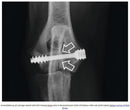

Die beiden Gewinde dieser Titan-Schraube haben eine unterschiedliche Ganghöhe, was dazu führt, daß beim Einschrauben zwischen den Knochenfragmenten eine Kompression ausgelöst wird. Zusätzlich zu dieser, von der Veterinary Tissue Bank (VTB) entwickelten Schraube für die IOHC, benötigt man DBM-Knochenkitt, der in den Hohlraum des Bohrkanals zwischen der Schraube und dem Knochen eingebracht wird und so die Heilung fördert. Diese Schraube kann auch bei der Versorgung von inter-condylären Frakturen von Hunden in der Größe eines Springer Spaniels (~ 25kg KGW) verwendet werden. Obwohl die Schraube selbstschneidend ist, empfehlen wir, vor allem bei sklerotischem Knochen, die Verwendung eines 4,5 mm Gewindeschneiders. Der Durchmesser des mittleren Schaftabschnittes ist kleiner, wodurch sich zwischen der Schraube und dem umgebenden Knochenmaterial ein Hohlraum bildet, der mit dem mitgelieferten DBM-Knochenkitt ausgefüllt wird. Durch diesen wird die Osteogenese induziert und unterstützt. IOHC – Schraube mit dem abgestuften Spezialbohrer. Zusammenfassung der Operationstechnik: - Ein medial und lateral kombinierter Zugang wird gemacht. - Eine 2,0 mm trans-condyläre Pilotbohrung wird von medial nach lateral gebohrt. - Mit dem Spezialbohrer wird von medial eine Bohrung gemacht, in der die IOHC-Schraube eingesetzt wird. - Die Schraube wird mittels eines 3,5 mm Hex-Schraubendrehers von medial in den Bohrkanal geschraubt. - Bevor der Schraubenkopf im Knochen eingreift, wird der Knochenkitt mit einer Spritze und einer 16 g Nadel von medial in den Raum zwischen Schraube und Knochen eingebracht. - Die Schraube wird angezogen, bis sie gut im Knochen sitzt. Beim Erwerb einer IOHC-Schraube bekommen Sie eine ausführliche Anleitung mitgeliefert.